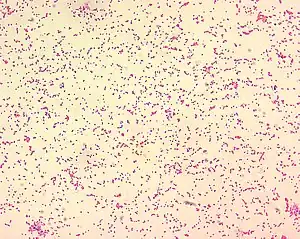

Brucella spp. are gram-negative in their staining morphology. Brucella spp. are poorly staining, small gram-negative coccobacilli (0.5-0.7 x 0.6-1.5 µm), and are seen mostly as single cells and appearing like "fine sand".